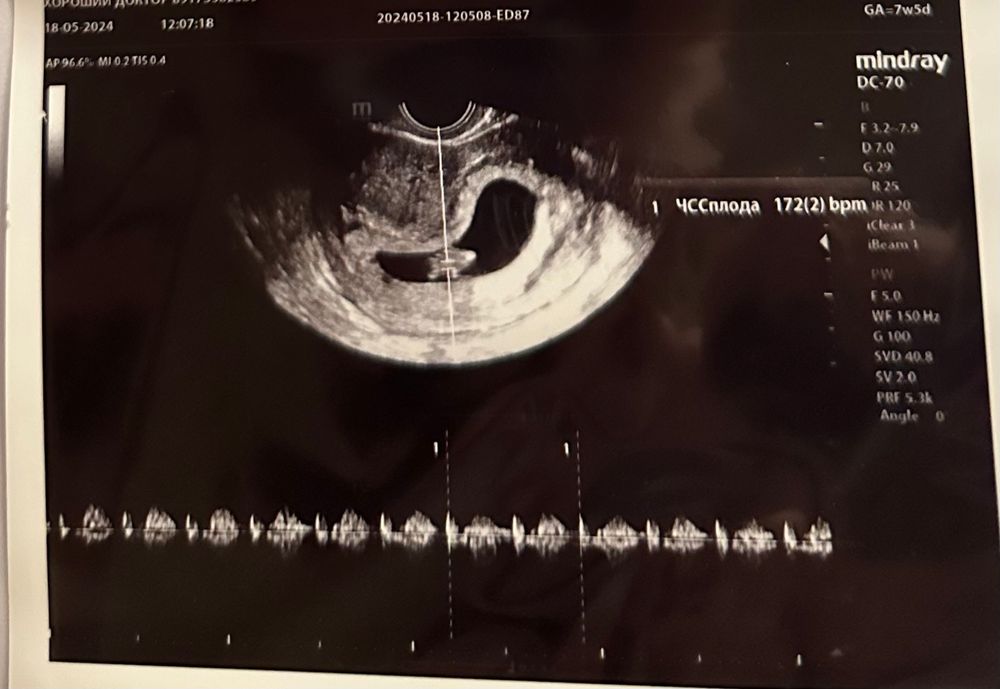

Растем) первое узи

Первое узи в 7н5дн, но по ктр опережает примерно на неделю. Все остальное пока в порядке.

И как от такого маленького человека может рвать 5 раз на дню😂